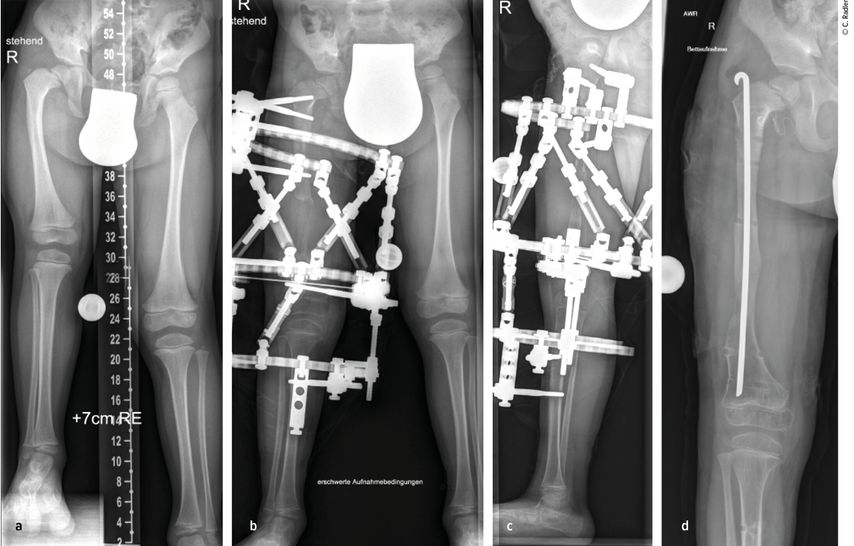

Milde Formen – Typ 1A – zeigen oft nur einen leichten Schenkelhalsvarus und eine verminderte femorale Antetorsion beziehungsweise Retroversion zusätzlich zur Verkürzung. Oft zeigt sich bei diesem Typ auch eine milde subtrochantäre Varusstellung und Sklerose. Mit zunehmendem Schweregrad addiert sich eine azetabuläre Dysplasie, wobei besonders die obere und hintere Überdachung der Hüfte vermindert ist. Beim Typ 1A ist in seltenen Fällen keine vorbereitende Operation erforderlich, insbesondere wenn die Überdachung der Hüfte sehr gut ist und ein CE-Winkel von über 20 Grad vorliegt. Es kann dann direkt mit einer Verlängerung des Femurs begonnen werden. Je nach verwendeter OP-Technik können eine eventuell vorhandene Retroversion und Varusstellung im Rahmen der Verlängerungsoperation akut über eine zusätzliche proximale Osteotomie und Montage an den oberen Teil des Fixateurs adressiert werden. (Abb.1).

Abb. 1: Operative Versorgung eines CFD rechts mit Varusstellung an der Hüfte und subtrochantärer Sklerosierung